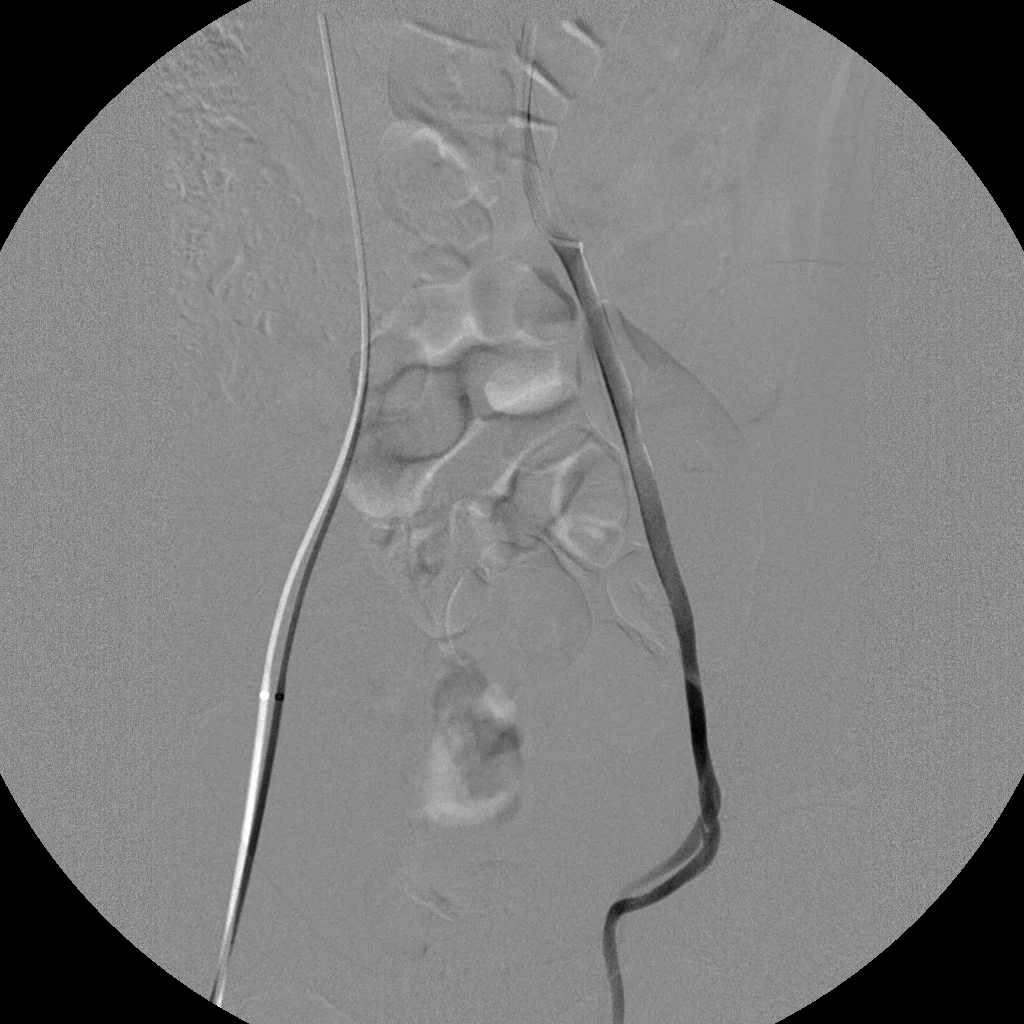

Venous Embolization: Case 1

23 year old male with left testicular discomfort and palpable veins.